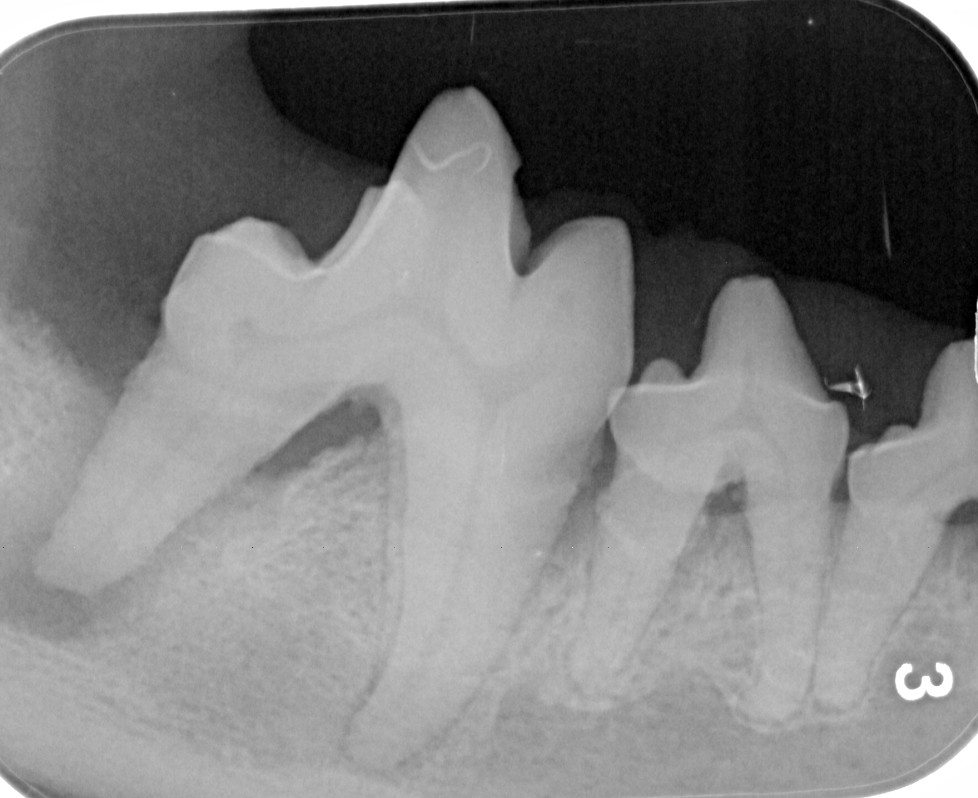

This dog has a slab fracture of the upper fourth premolar, one of the most common fractured teeth in dogs. These fractures often expose the pulp cavity, which can lead to infection and pain if not treated.